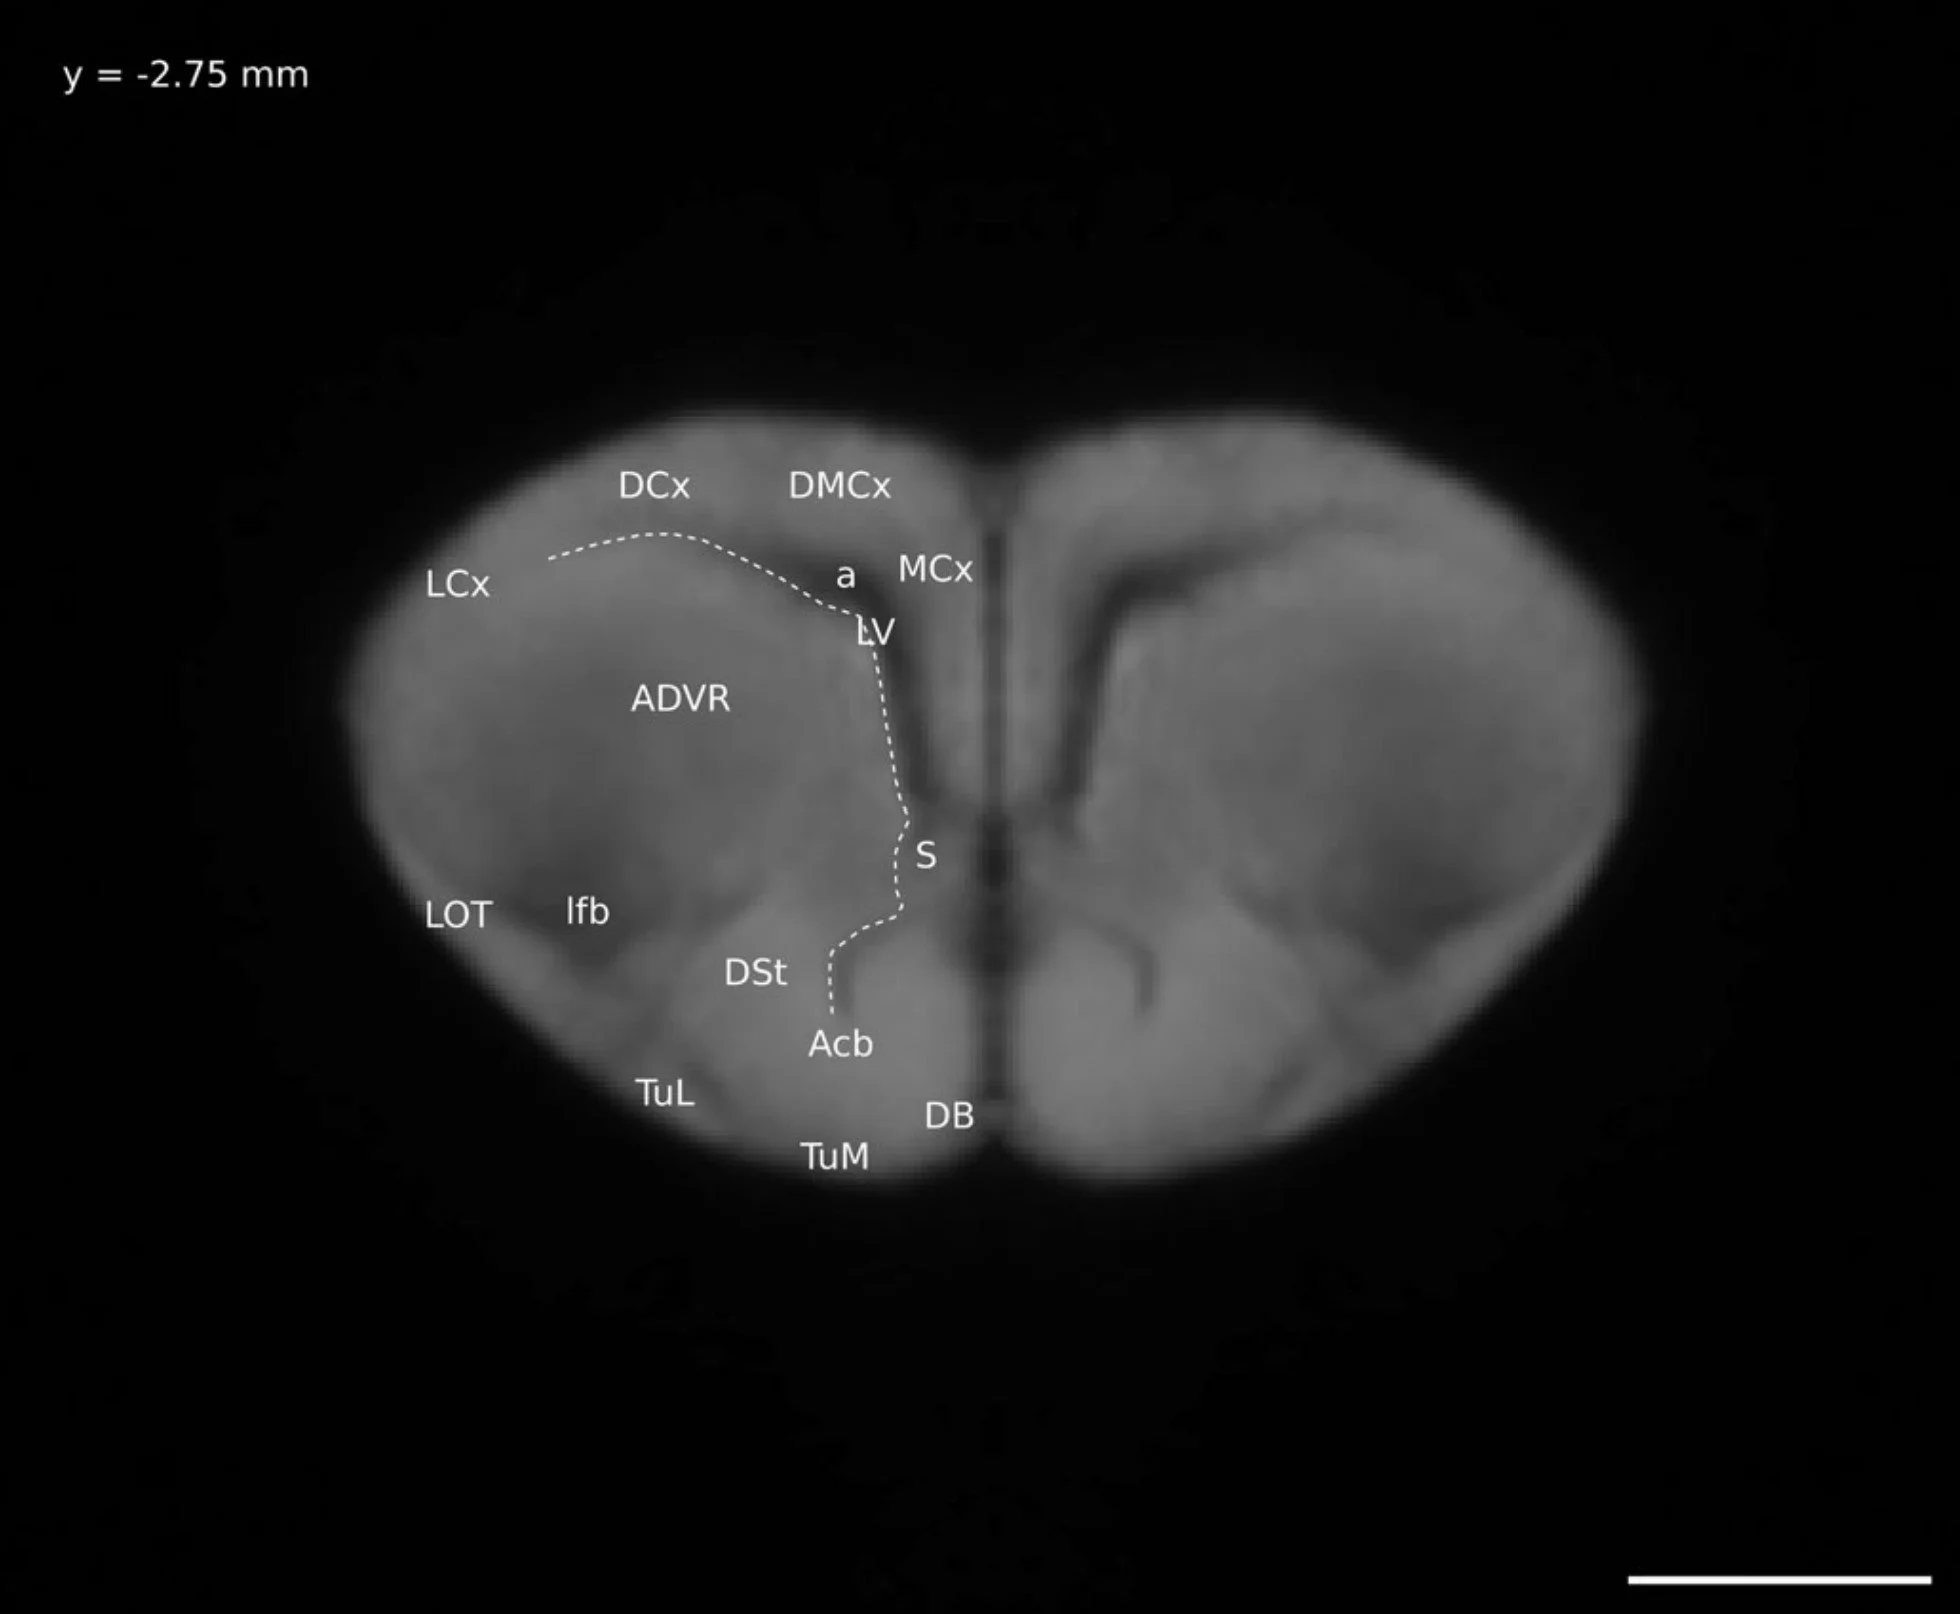

This is the window that I will call the 3-views window. It shows, clockwise from top left: sagittal view, coronal view, intensity plot, and transverse view. On the left there is a scale bar showing the range of intensity values in the image and below that details about the specific voxel over which the cursor is hovered.

I need to find the minimum and maximum intensity values for my image - the values that correspond to black and white, respectively. On the left-hand side of the window that shows the three views of my image is a scale bar. At the bottom is black and the top is white. Near the bottom of the scale bar is a little green line, with a number beside it, 262.136. By hovering my cursor over the bar (not the number) my cursor turns into a hand, and I then click on the line and drag it all the way to the bottom of the scale bar. The number beside it is now 0, my minimum (black) value. Near the top of the scale bar is a little blue line with the number 32406.6 beside it. I click on the line and drag it to the top of the scale bar, it now shows 32767, my maximum (white) value.